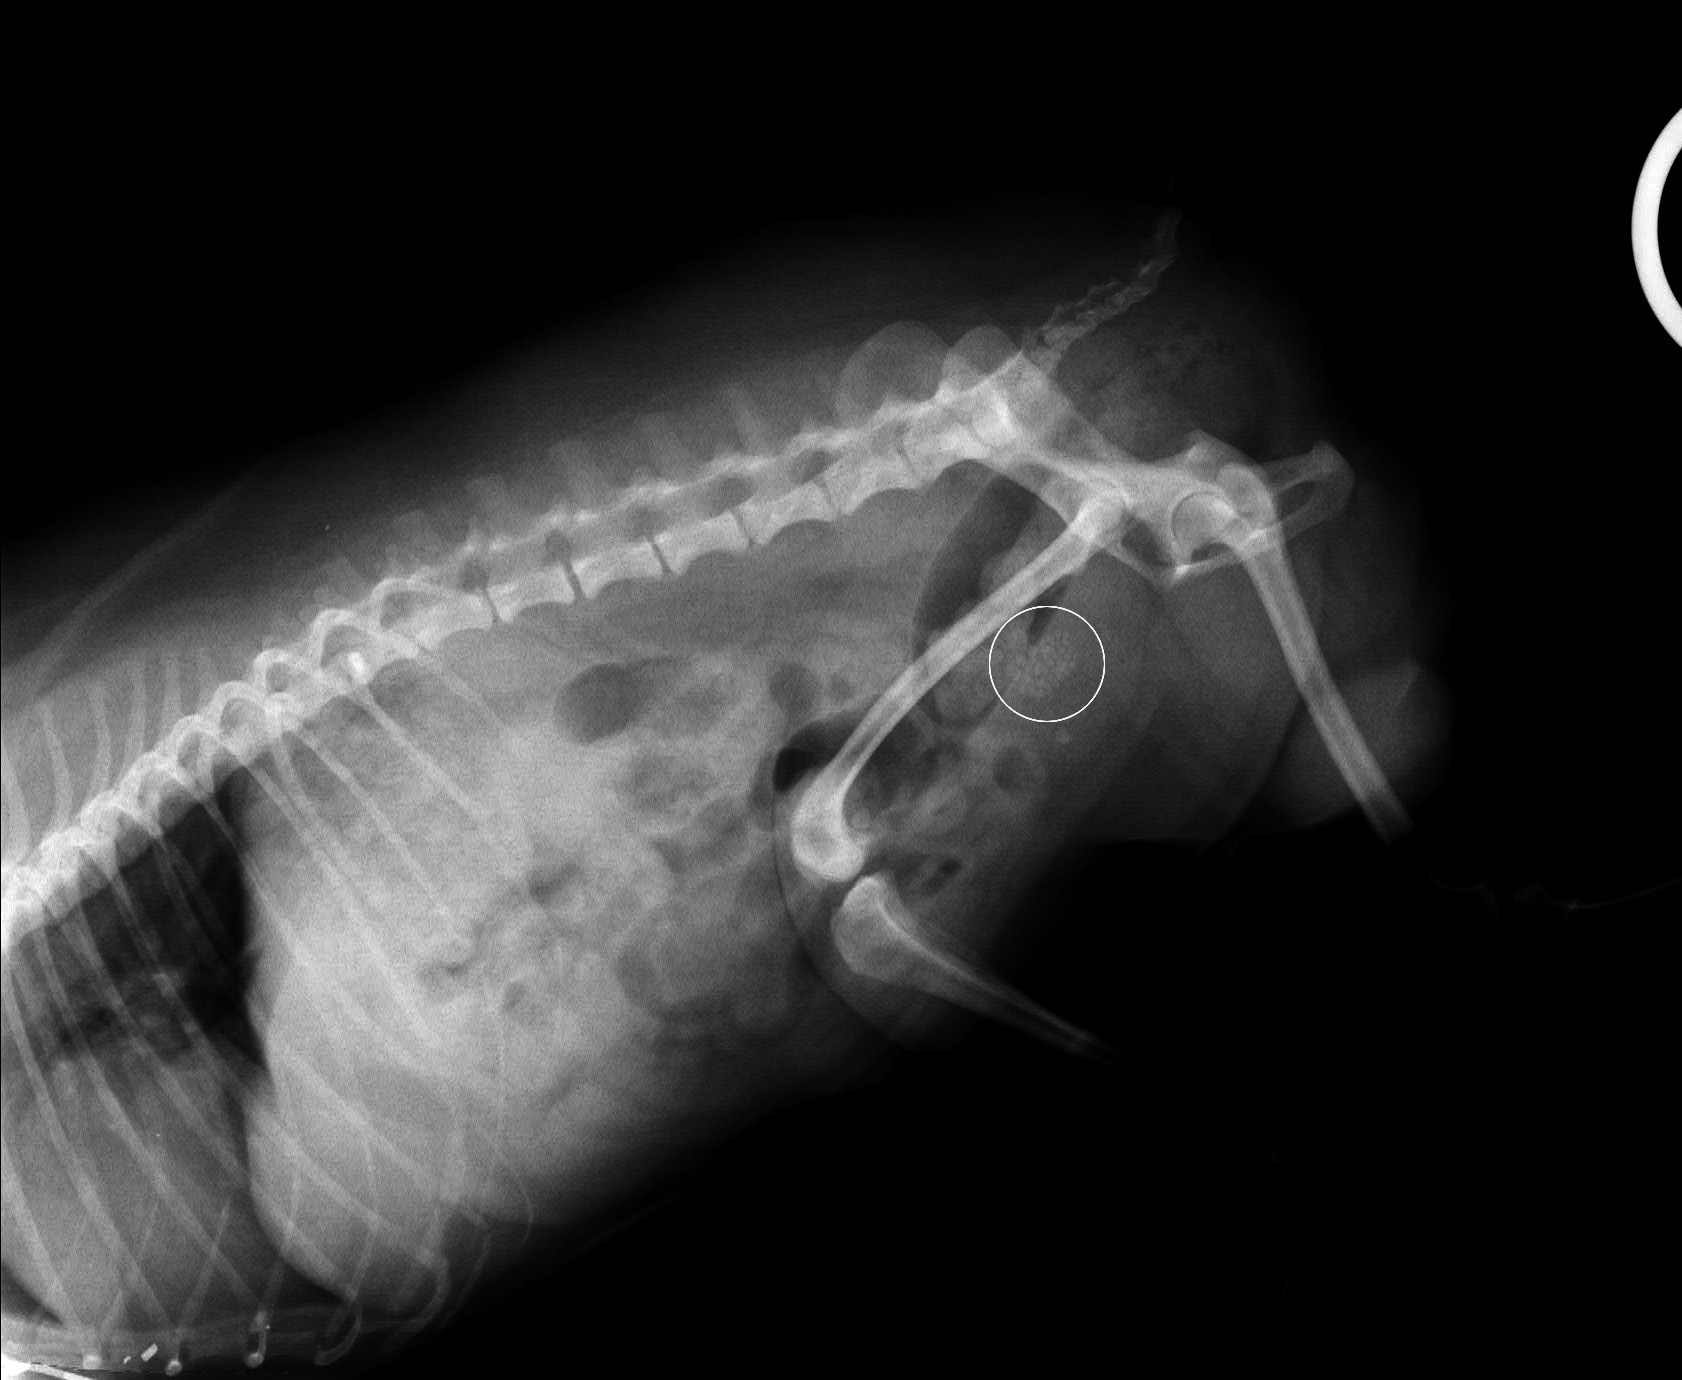

ポメラニアン オス6才 にできた膀胱結石

1mm大の結石が多数